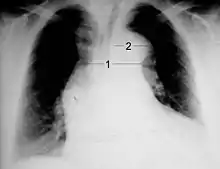

فحص الصدر بأشعة اكس

يتميز اختبار الكشف عن اتساع منطقة وسط الصدر (اتساع المنصف) باستخدام أشعة اكس لفحص الصدر بدرجة متوسطة لخاصية الحساسية (تبلغ نسبتها %67)، وذلك عند تشخيص تسلخ الأبهر الصاعد.[10] وعلى الرغم من ذلك، يتميز هذا الإجراء بدرجة منخفضة لخاصية النوعية؛ وذلك لأن العديد من الحالات المرضية الأخرى يمكن أن تتسبب في حدوث اتساع المنصف الذي يظهر عند فحص الصدر بأشعة أكس.

يرجح وجود الدليل المرضي الذي يعبر عنه ظهور الكالسيوم عند فحص الصدر باستخدام أشعة اكس أن الشخص الذي يتم فحصه مصابًا بتسلخ الأبهر. وينتج ذلك عن انفصال التكلس البطاني لجدار الشريان الأبهر عن حافة النسيج الأبهري الرخو بمقدار 10 ملليمترات.

وقد تظهر ارتشاحات بلورية عند فحص الصدر بأشعة اكس. وعادةً ما تظهر تلك الارتشاحات في حالات تسلخ الأبهر الهابط. فإذا ما ظهرت الارتشاحات في صور الأشعة، فإنها عادةً ما تظهر في شق الصدر الأيسر.

أما النتائج الأخرى التي يمكن اكتشافها باستخدام أشعة اكس على الصدر، فهي: انطماس الظل الخاص بقوس الأبهر على صورة الأشعة (aortic knob) اختفاء العقدة الأبهرية وهبوط الشعب الهوائية اليسرى، واختفاء الخطوط المجاورة للرغامي، وانحراف الرغامي.

وتظهر صورة فحص الصدر بأشعة اكس "طبيعية" في نسبة تتراوح ما بين %12 و%20 من المصابين بتسلخ الأبهر.